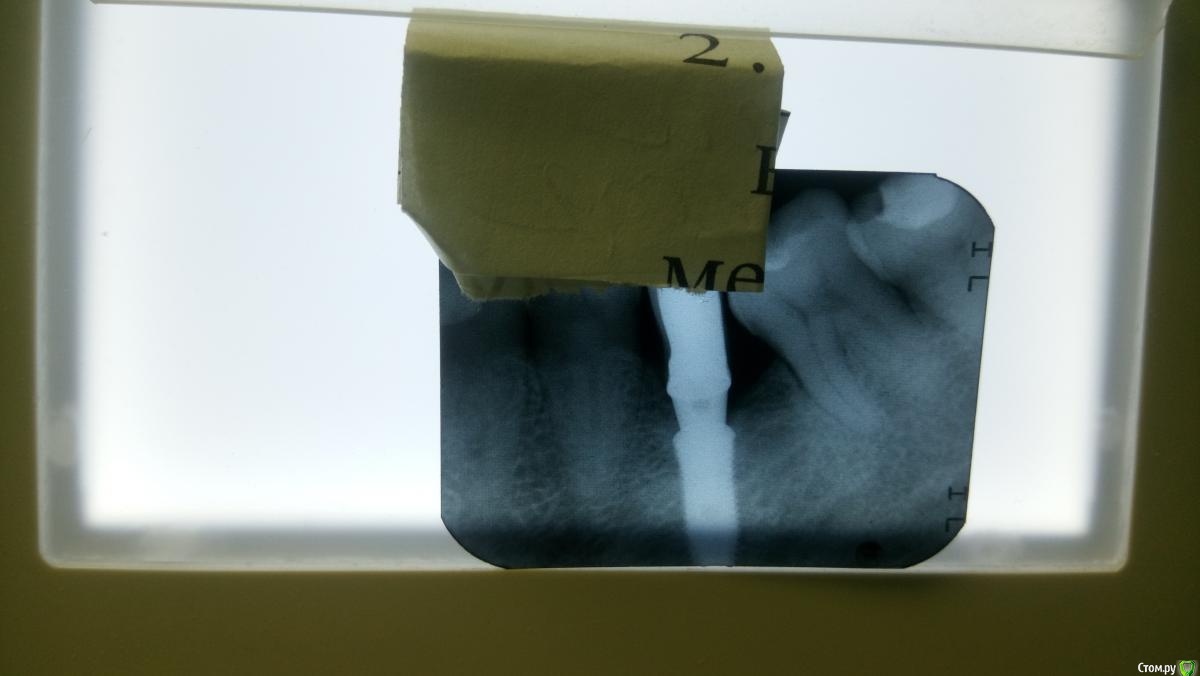

zubovolok Опубликовано 21 апреля, 2016 Автор Поделиться Опубликовано 21 апреля, 2016 Снимок после пришлифовки "юбки", ещё немного в полости рта пришлифую и хватит. Ссылка на комментарий